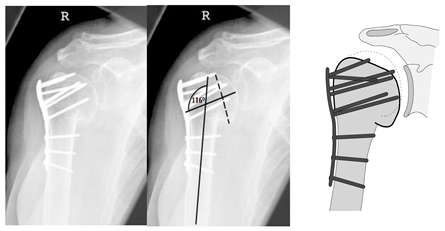

| Complication Type | Exemplary Images by X-rays or Pattern Images | Definition |

|---|---|---|

| 2b | ![]() | Complication Type 2b is limited to displacement of the greater tuberosity, lesser tuberosity, or both tuberosities. |

| 3 | ![]() | Type 3 describes a displacement of the angular stable plate osteosynthesis with screw cutout/fracture avulsion in the humeral shaft region, while the humeral head position remains intact. |